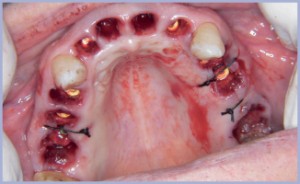

Si optava per la rimozione di tutti gli elementi dentali superiori, del gruppo frontale inferiore e di 45-47-48, con posizionamento di 8 impianti sul mascellare superiore e di 4 sulla mandibola (figg. 7-11).

- Figg. 8, 9 – Chirurgia flapless e post-estrattivi immediati

Gli impianti erano da posizionare contestualmente alle estrazioni dentali ed in chirurgia flapless. Minirialzi erano necessari sull’emiarcata superiore sinistra.